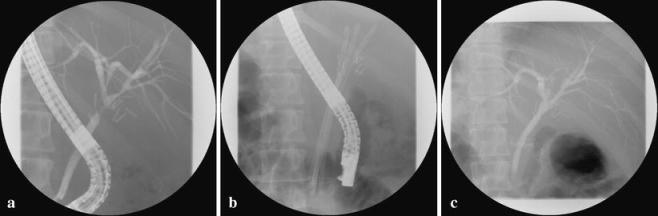

The management of a bile duct injury detected during laparoscopic cholecystectomy is still under discussion. An end-to-end anastomosis (with or without T-tube drainage) in peroperative detected bile duct injury has been reported to be associated with stricture formation of the anastomosis area and recurrent jaundice. Between 1991 and 2005, 56 of a total of 500 bile duct injury patients were referred for treating complications after a primary end-to-end anastomosis. After referral, 43 (77%) patients were initially treated endoscopically or by percutaneous transhepatic stent placement (n = 3; 5%). After a mean follow-up of 7 +/- 3.3 years, 37 patients (66%) were successfully treated with dilatation and endoscopically placed stents. One patient died due to a treatment-related complication. A total of 18 patients (32%) underwent a hepaticojejunostomy. Postoperative complications occurred in three patients (5%) without hospital mortality. These data confirm that end-to-end anastomosis might be considered as a primary treatment for peroperative detected transection of the bile duct without extensive tissue loss. Complications (stricture or leakage) can be adequately managed by endoscopic or percutaneous drainage the majority of patients (66%) and reconstructive surgery after complicated end-to-end anastomosis is a procedure with relative low morbidity and no mortality.

腹腔镜胆囊切除术中发现的胆管损伤的处理仍在讨论中。据报道,术中发现的胆管损伤行端端吻合术(带或不带T管引流)与吻合口狭窄形成和复发性黄疸有关。1991年至2005年期间,500例胆管损伤患者中有56例在初次端端吻合术后因并发症前来治疗。转诊后,43例(77%)患者最初接受内镜治疗或经皮经肝支架置入术(3例,5%)。平均随访7±3.3年后,37例(66%)患者通过扩张和内镜置入支架成功治疗。1例患者因治疗相关并发症死亡。共有18例(32%)患者接受了肝空肠吻合术。3例患者(5%)出现术后并发症,无医院死亡病例。这些数据证实,端端吻合术可被视为术中发现的无广泛组织损失的胆管横断的主要治疗方法。大多数患者(66%)的并发症(狭窄或渗漏)可通过内镜或经皮引流得到充分处理,复杂端端吻合术后的重建手术是一种发病率相对较低且无死亡率的手术。